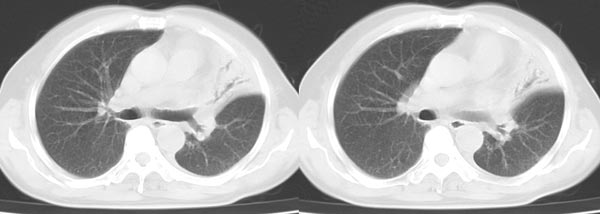

以下是引用dyqct在2006-4-1 22:20:00的发言:[br]左肺上叶明显萎陷、实变,支气管大部通畅,部分扩张,部分壁似见串珠状钙化。主动脉弓旁见肿大淋巴结。纵隔左移。左侧胸壁后缘见新月形高密度,边界清楚。[br] 考虑:1、左肺上叶肺不张伴支气管扩张(牵拉性),可能为支气管内膜结核所致。[br] 2、左侧少量胸腔积液。[br]

以下是引用piao001在2006-4-2 14:13:00的发言:[br]左肺上叶不全性不张,其内见钙化及扩张支气管,结合病史,考虑支气管内膜结核。建议支气管镜明确检查。